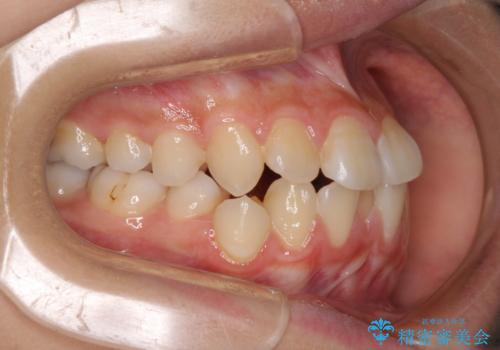

- 下顎の前突感と前歯の叢生を気にして来院された患者様です。

下顎前方位の骨格のため、下顎歯列に対して上顎歯列の幅が狭くなっていました。

急速拡大装置を用いて上顎骨を側方に拡大し、上顎の叢生を解消するとともに下顎歯列拡大により下顎の叢生も解消することとしました。

上顎骨を拡大しない場合には、奥歯に咬みにくさが残ったり、下顎前歯の歯肉退縮や口元の突出感などが出たりと、妥協的な仕上がりとなります。